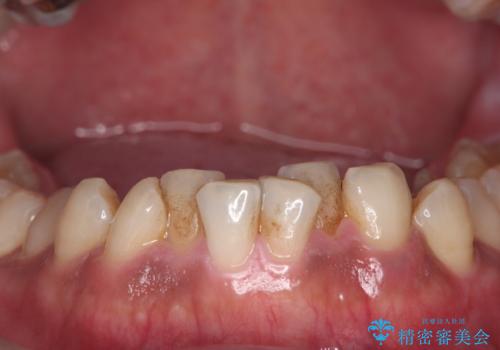

コーヒー、タバコなどで着色した歯をPMTCで、きれいに!!

- 長年の喫煙とコーヒーによる歯の、着色をとりたいと来院されました。

かなり汚れがこびりついていたので、PMTC(歯科医院で行うプロフェッショナルクリーニング)60分コースを

おすすめしました。

歯の着色だけでなく、汚れもとれ歯の表面がツルツルなって気持ちがいいと

大変満足していただけました。